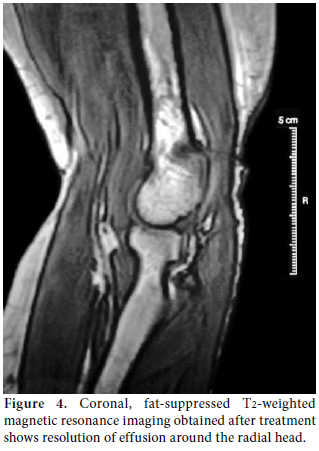

The diagnostic approach, including a careful clinical examination, non-invasive imaging techniques (US, MRI), and electrophysiological assessment were sufficient to obtain the diagnosis of PIN palsy. The patient refused to be assessed surgically, so we reconsidered and rearranged her medication by increasing the methotrexate dosage to 15 mg/week and also subcutaneously, drained the fluid and injected methylprednisolone acetate (40 mg/mL) intra-articularly by using the lateral approach to the center of the triangle formed by the lateral olecranon, the head of the radius, and the lateral epicondyle.[7] The patient was followed up via clinical, US and electrophysiological assessments every three months. Her symptoms improved the second month after the injection, and they completely resolved at the sixth month without surgical intervention. The ultrasonographic resolution was noted at the third month, but better recruitment was obtained at sixth month from the affected muscles. However, fibrillation potentials remained albeit with a smaller amplitude size. Revisualization by MRI, repeated at the 18th month, detected resolved effusion with clinical stability (Figure 4).